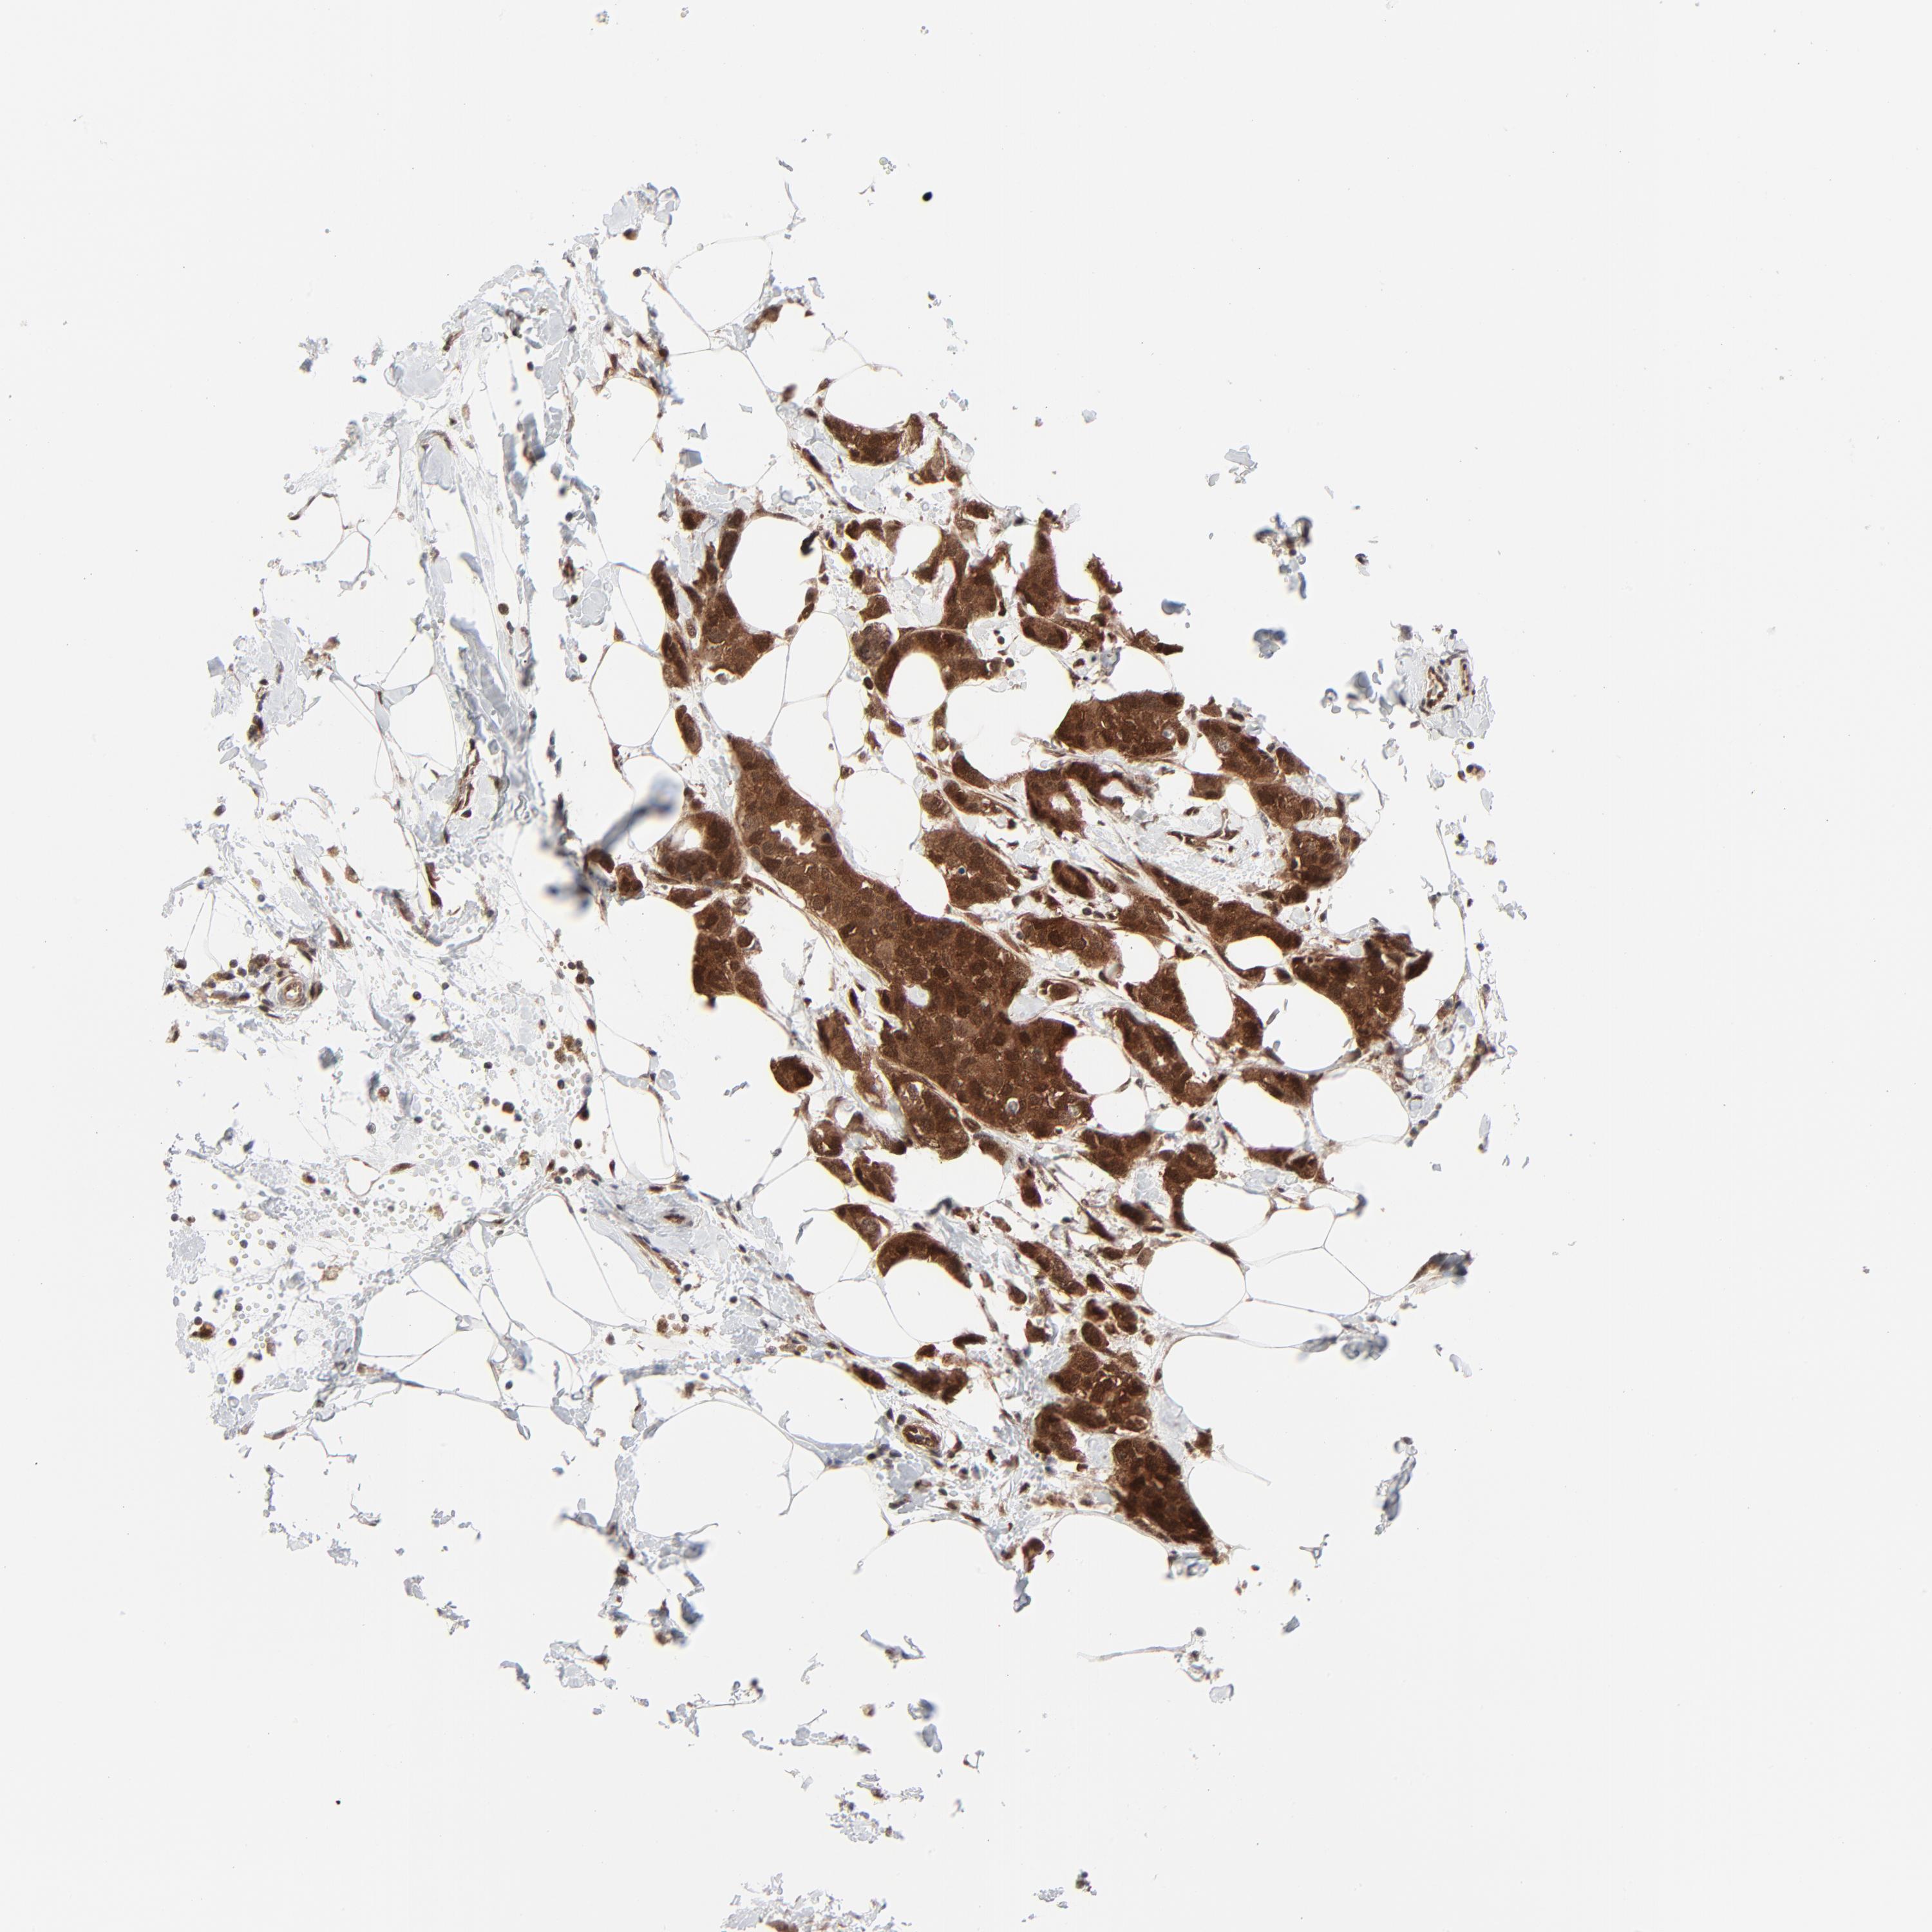

BRCA TCGA BRCA VALIDATION PROTEIN EXPRESSION